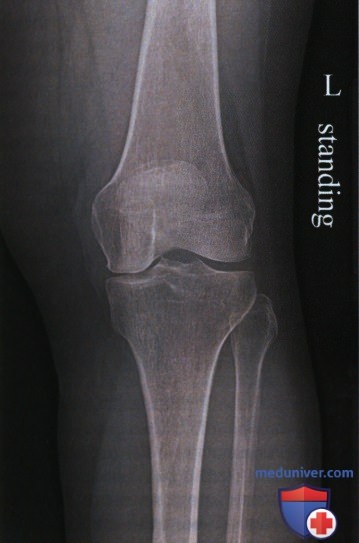

Медицинские снимки: рентген коленного сустава при остеопорозе